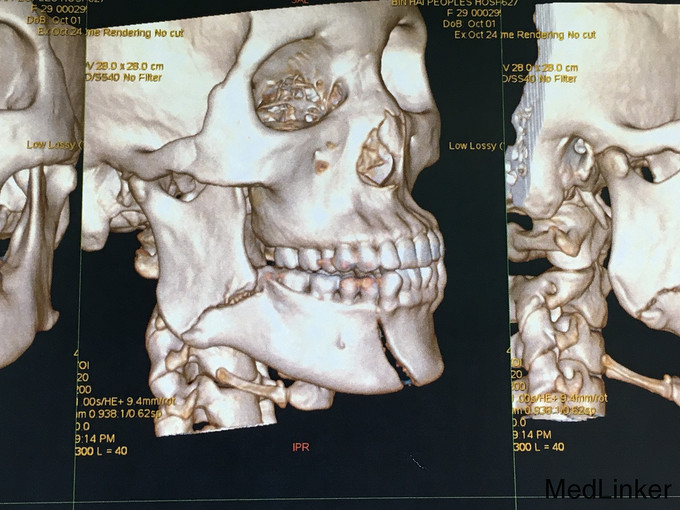

查体:神志清楚,右下颌体部见长约2.0cm开放创口,张口度1.5cm,咬合关系紊乱,右下唇麻木感,43,44间见明显骨折线,异常动度,48松动II,牙龈撕裂,右下颌肿胀,右侧髁状突冲击试验减弱,上颌骨无异常动度,于无异常。 辅查:CT,右下颌骨颏部及下颌角不骨折。

诊断:右下颌骨颏部及下颌角不骨折 治疗:右下颌骨颏部及下颌角部骨折经口内切开复位内固定。